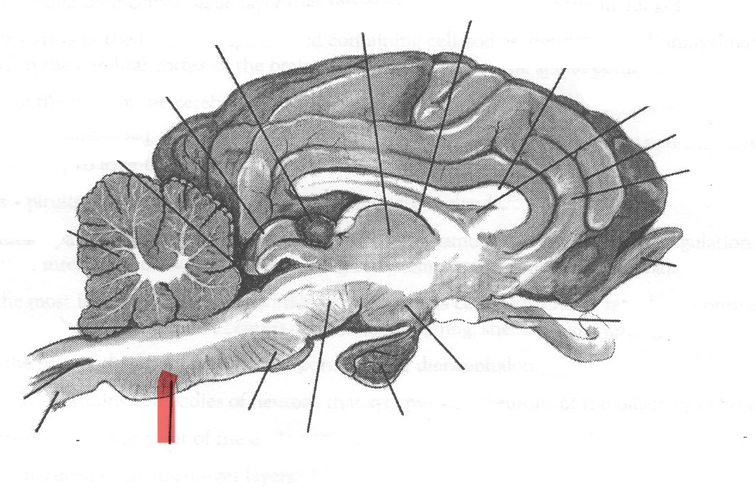

Identify highlighted arrow

Medulla